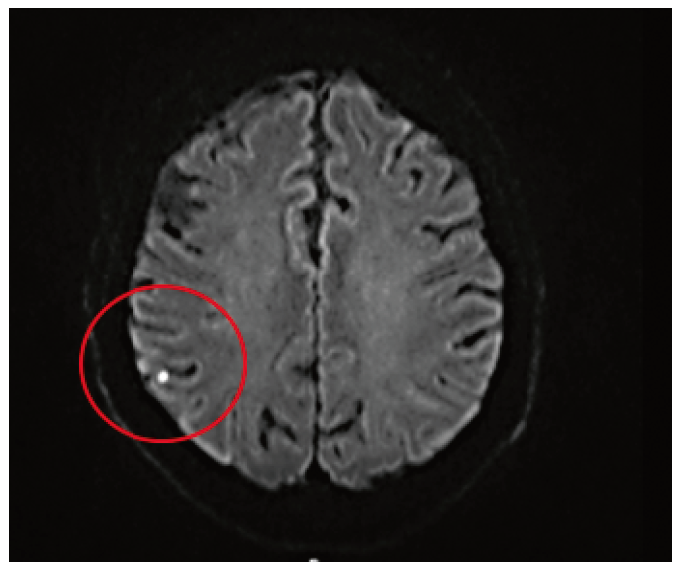

4. Fig. 4. Acute foci of ischemia in a patient with type 2 diabetes according to diffusion-weighted magnetic resonance imaging 24 hours after carotid endarterectomy in the cortical substance of the frontal and parietal lobes of the right hemisphere of the large brain.